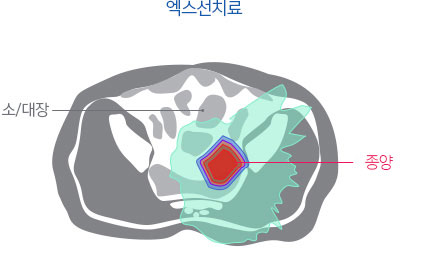

엑스선치료로는 고선량 치료가 어렵고, 부작용이 흔함.

이미 방사선치료가 시행된 재발 직장암의 경우 종양 제거가 어렵고, 수술의 경우 미용적, 기능적 제한이 큰 것으로 알려져 있습니다. 따라서 고선량의 방사선 재 치료가 시행되는 경우가 많은데, 이 경우 세기조절 방사선치료를 시행하더라도 주변 정상 장기에 노출되는 방사선으로 인한 부작용이 흔하며, 총 방사선량이 제한되어 5년 종양 제어율이 50% 이하로 알려져 있습니다. 하지만 주변 정상 장기에 방사선 노출을 크게 낮출 수 있는 양성자치료는 부작용에 대한 우려를 낮추면서 고선량의 방사선을 전달하여 종양을 제거할 수 있을 것으로 기대하고 있습니다.